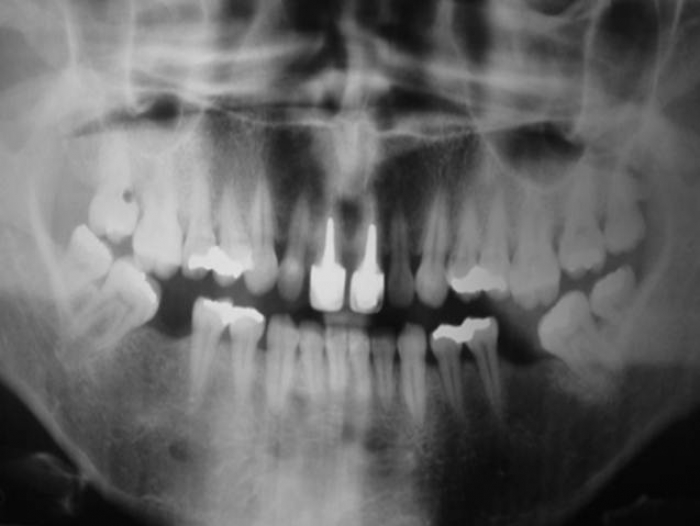

Imagens do caso inicial, com presença de fratura radicular do dente 21

Raio X inicial